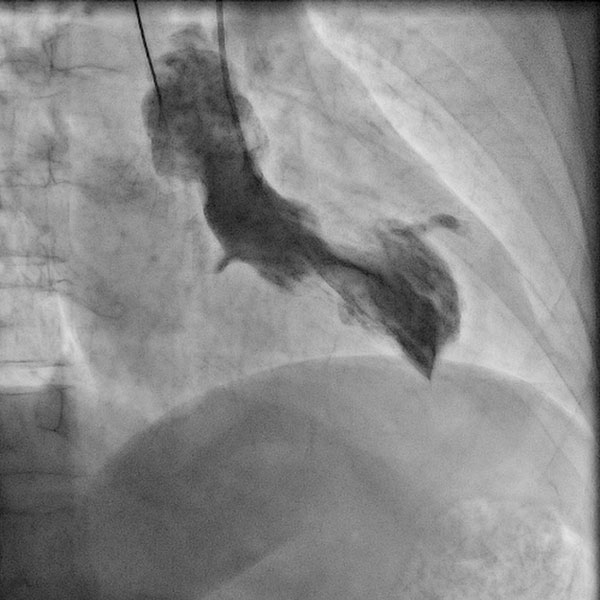

A 65-year-old woman with a history of diabetes, hypertension and smoking, presented a 2-day history of severe chest pain. EKG showed septal necrosis and anterolateral ST segment elevation. Under presumed diagnosis of ST segment elevation myocardial infarction (STEMI), she was transferred to the cardiac catheterization laboratory, painless. Occlusion of a diagonal branch and proximal circumflex lesion were identified. Percutaneous coronary intervention of the circumflex artery was performed. She was transferred to an intermediate care unit. Twelve hours after the procedure, the patient referred recurrent chest pain, a new ST segment elevation was observed. Coronary angiography was performed, verifying patent stent.

An image is worth a 1000 words: tell us what you see in this image!